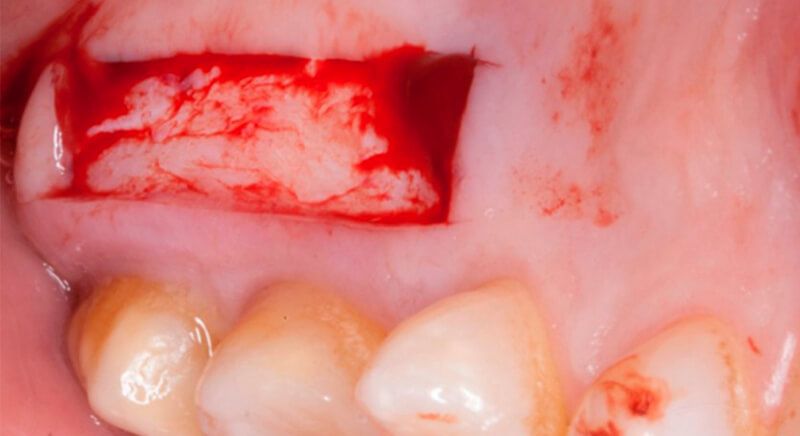

The socket was filled with a xenograft after the extraction and a graft of connective tissue was placed in the vestibular area of the two upper central incisors.

The tissue with epithelium was taken from the palate and de-epithelialized outside of the mouth. This obtains a lamina propria graft with better density and quality than if it were obtained with a single incision to the palate.